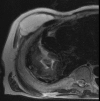

Empyema necessitans is a rare clinical finding nowadays. We report the case of a patient admitted in our ward for investigation of an unknown onset anterior chest wall mass, with no accompanying signs or symptoms. It is noteworthy that the patient had had pulmonary tuberculosis submitted to thoracoplasty more than 60 years before. Thoracic MRI showed a large heterogeneous mass, with a thick wall and internal septations located at the right anterior chest wall, as well as a heterogeneous content inside the right pleural cavity, with direct communication between both. An aspirative puncture of both masses was performed, with positive cultures for Mycobacterium tuberculosis, thus leading to the diagnosis of pleural tuberculosis with anterior chest wall empyema necessitans. A drain was inserted and antibiotics started. This case draws our attention to a very rare complication of pulmonary tuberculosis and its surgical treatment, though it aroused many decades after primary infection.